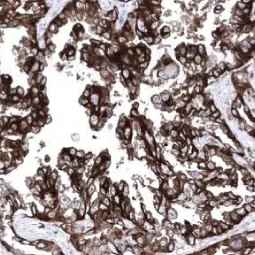

With this in mind, GeneTex is proud to introduce its HistoMAX product line that consists of antibodies specifically vetted for IHC. All of these reagents were extensively evaluated for IHC utilizing formalin-fixed normal and cancer tissue microarrays to guarantee specificity and best-in-class performance. Only antibodies that have passed these stringent performance criteria for IHC will be added to the HistoMAX portfolio.![]()